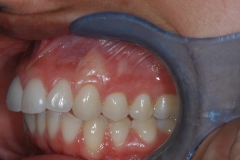

This mouth had recession on just one tooth with very little bone to support the tooth. The area needed support and thickness. The tissue was placed and the area now has thicker tissue to withstand the forces that the patient needs to place on it.

Click on a thumbnail to view the before and after photos.